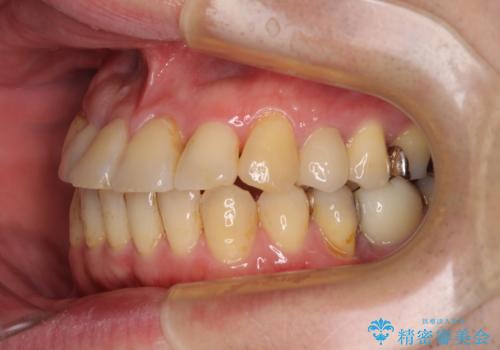

矯正治療でインプラント埋入を行い、矯正治療後に気になる前歯と合わせてオールセラミッククラウンによる補綴治療を行うこととしました。

骨造成や歯肉移植など、治癒期間の長い処置を必要としたため治療期間は長くなりましたが、安定した咬み合わせと整った歯列となり、患者様には大変満足していただきました。